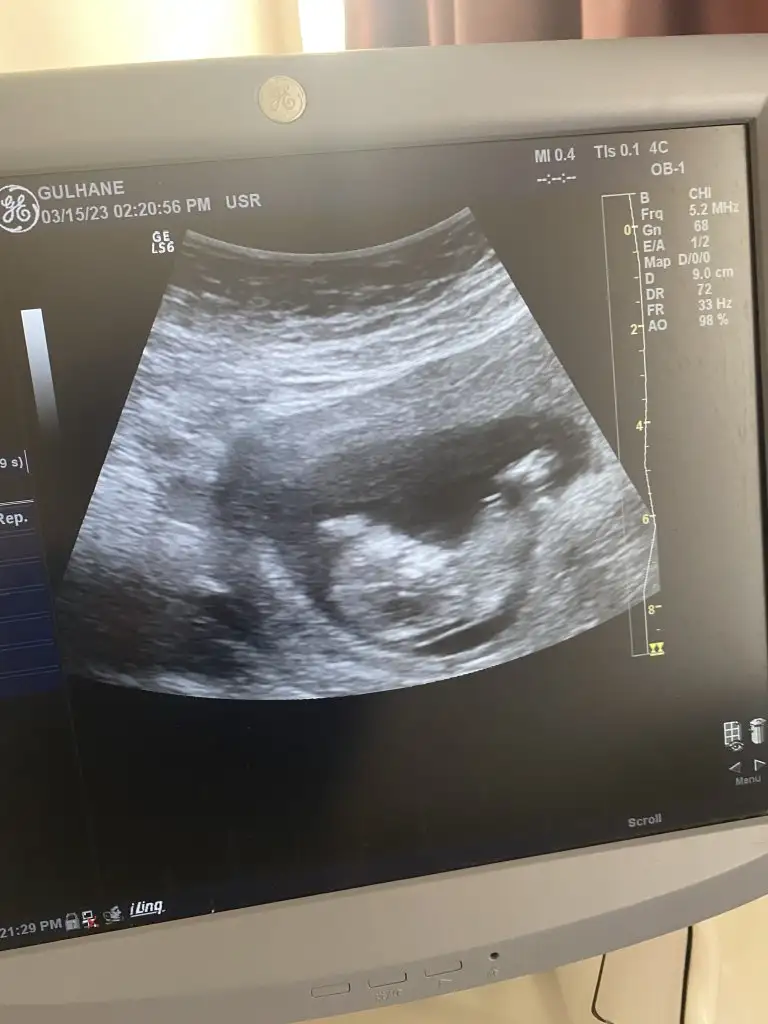

Onun dışında küçük fasülyem iyiymiş keyfi yerindeymiş minicik bir karaltı da olsa gördük kendisini kalbini de duyduk. Babası sabahtan beri delirmiş gibi durmadan kaydettiği kalp sesini dinliyor

Banada bakarmısın 12 haftalıkerkek askım :)

Ramzı ıcın 12 hafta buyuk kuzum 7-10 arası varsa bakayımBanada bakarmısın 12 haftalık

Kız canımBu var 7 hafta 3 günlük

Yarın cinsiyeti öğrenince yazarım teşekkürler şuan 14 haftalık